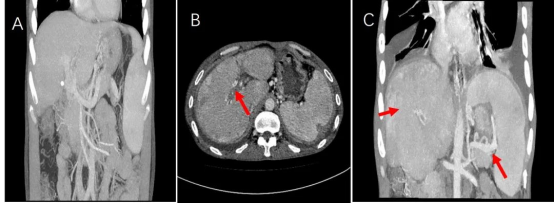

图4. 影像学检查

A图:2016年可见门静脉主干轻度狭窄,门脉期入肝血流侧枝丰富,肝脾强化均匀且基本一致;B、C图:2022年复查见门静脉主干狭窄明显加重(红色箭头),部分肝内分支基本消失;门静脉期大部分肝脏强化明显低于脾脏(红色箭头);门脉高压较前明显加重、食管胃底静脉曲张、脾肾分流静脉较前增粗明显。